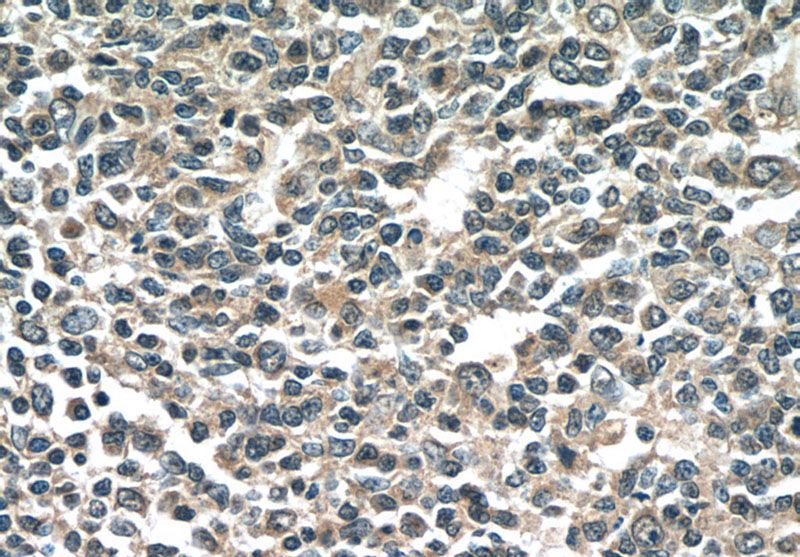

Immunohistochemistry of paraffin-embedded human tonsillitis tissue slide using Catalog No:107333(NINJ2 Antibody) at dilution of 1:50 (under 40x lens)